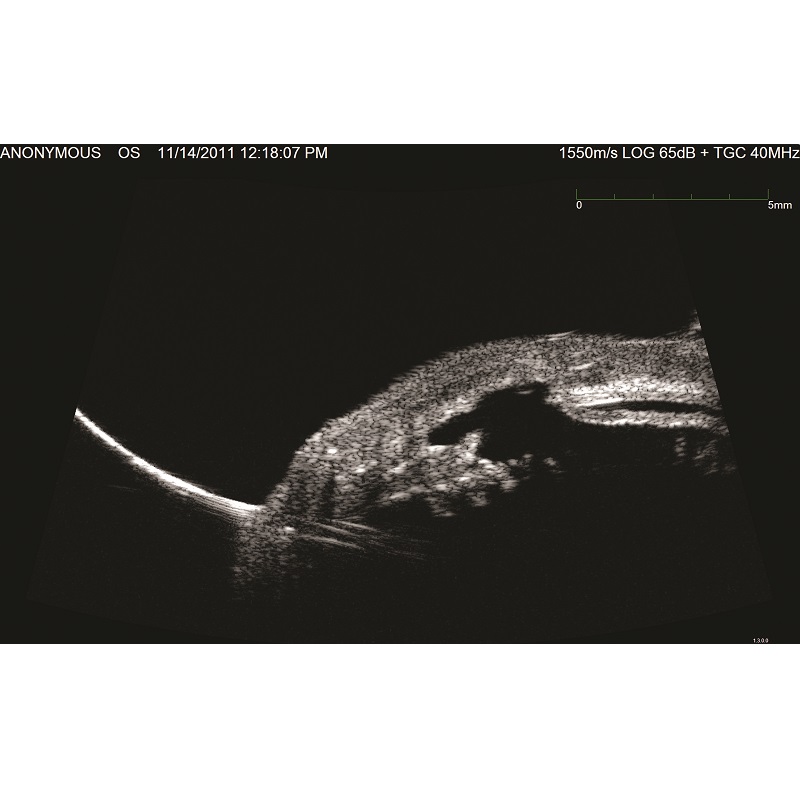

Dzięki dostosowanej konfiguracji trybów A-Scan i B-Scan, Eye Cubed spełnia wszystkie potrzeby w zakresie diagnostyki ultrasonograficznej zarówno w odcinku tylnym, jak i przednim. Tryb UBM 40 MHz umożliwia widzenie struktur oka wyraźniej niż kiedykolwiek wcześniej. Niezależnie od tego, czy mierzymy szczelinę między bruzdą w celu dokładnego określenia rozmiaru ICL, czy kąt przed irydotomią laserem YAG, jest to funkcja, która reprezentuje to, co najlepsze w ultrasonografii o wysokiej rozdzielczości. W trybie skanowania B-Scan 10 MHz Eye Cubed świetnie poradzi sobie z wykryciem nawet najmniej widocznych schorzeń.

UMB (tak/nie): Tak